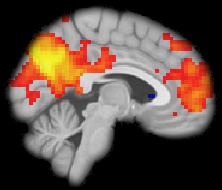

MT-sat

The MT-sat sequences are acquired at the same resolution, i.e. 1.7 mm iso, and in the same space as the diffusion data. This is to facilitate the two modalities being combined to create a map of the myelin g-ratio (the ratio between the inner and the outer diameter of the myelin sheath).

The MT-sat consists of an MToff sequence, an MTon sequence, and a T1-weighted sequence. The acquisition time for the first two sequences is 4 minutes each; the acquisition time for the T1-weighted sequence is 1:50.